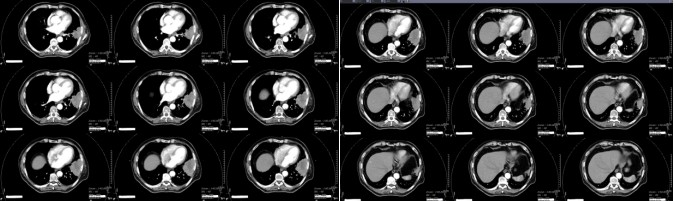

Chest CT on January 5, 2024 (before carbon ion therapy): Left lung tumor 8.6 × 6.0 × 6.0 cm